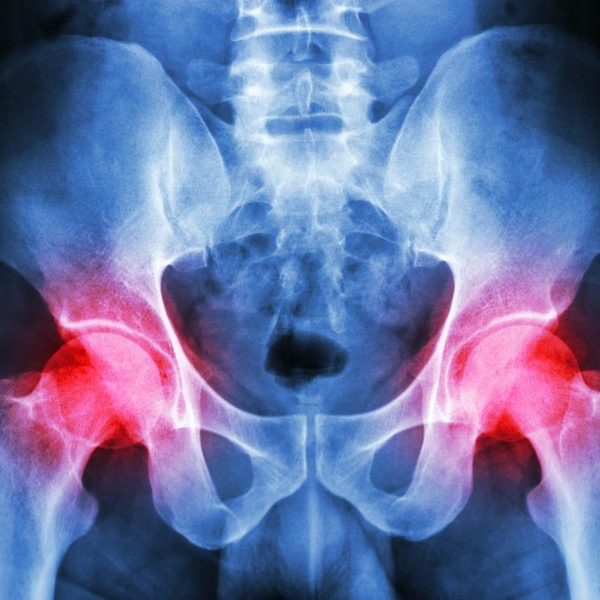

Find out the various factors responsible for pelvic pain

Pelvic pain is a pain in the lowest part of your abdomen and pelvis. The term pelvic pain is most commonly used to refer to pain arising from reproductive organs (uterus, fallopian tubes, ovaries, vagina) in women.

Several types of diseases and conditions can cause pelvic pain. Dr. Sushma Chawla says pelvic pain can result from more than one condition. Depending on its source, pelvic pain can be dull or sharp; it might be constant or off and on (intermittent); and it might be mild, moderate or severe.

The pain might be steady, or it might come and go. It can be a sharp and stabbing pain in a specific spot or a dull pain that is spread out. Pelvic pain can occur suddenly, sharply and briefly (acute) or over the long term (chronic).